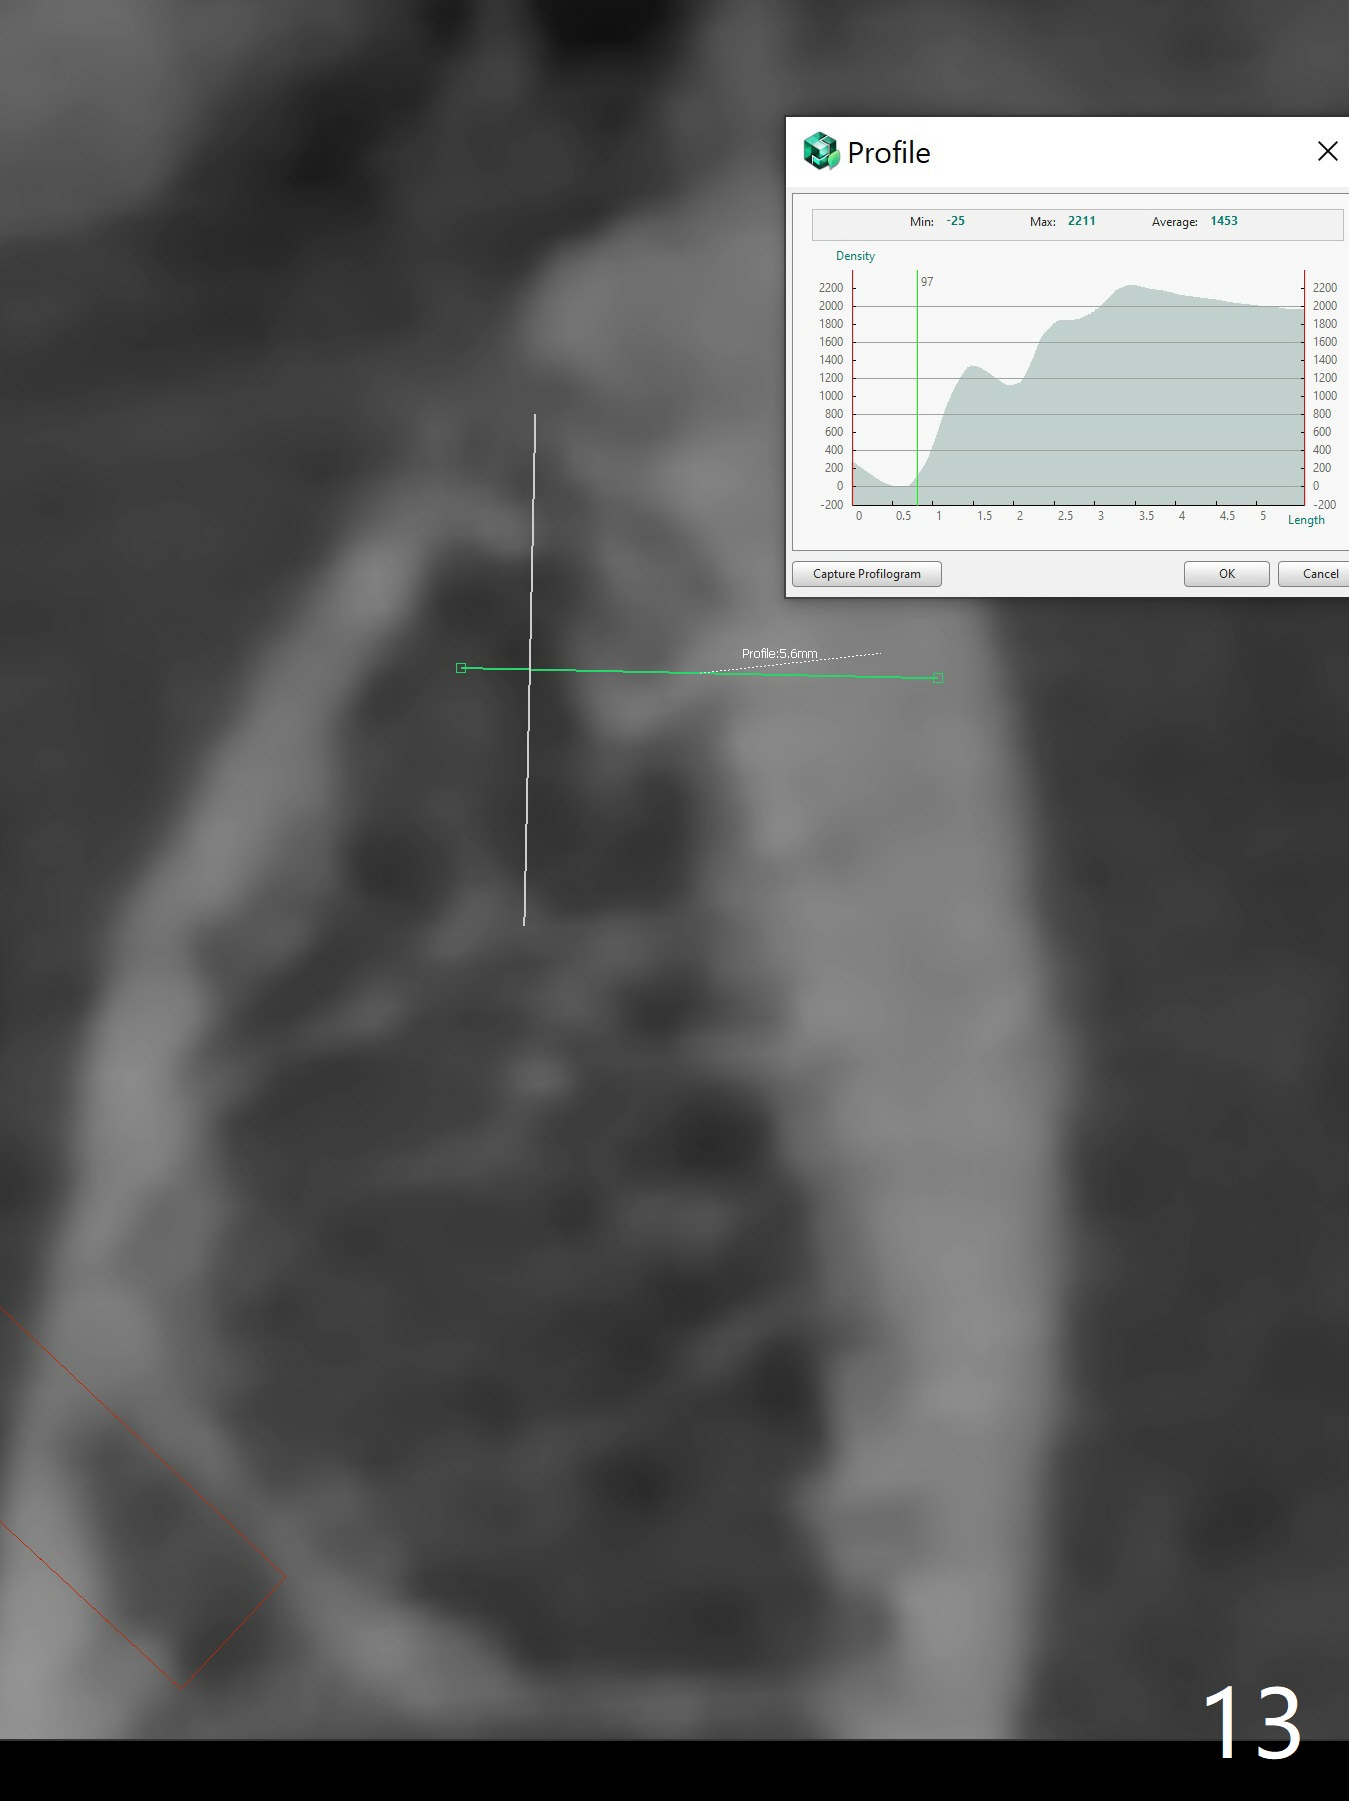

The extraction socket of #31 has a thin septum (Fig.2), which is removed partially with 12 mm bone trimmer (Fig.3). After placement of a 5x9 mm FC implant (~40 Ncm) and 6 mm bone profile drill, a 5.5x4(2) mm abutment is incompletely seated (Fig.5 <) and later is changed to a 4.5x1 mm temporary abutment (Fig.6, 8 T). The latter is used to fabricate a provisional, which in turn supports the distal papilla (Fig.8 *). The gingiva is slightly erythematous immediately post periodontal dressing removal (3 weeks postop, Fig.9). Take CT to confirm whether the cortical drill helps keep the #29 implant lingual. Use a profile drill at #29 if crestal bone loss is not obvious. There is bone coronal to #29 implant 4 months postop (Fig.10). Upon incision, the ridge is rounded (Fig.10'), but the implant appears to be buccally placed (Fig.10'' (post high speed handpiece and 5.5 mm profile drill)). The latter is confirmed by CT (Fig.12, as compared to design (Fig.11)). In spite of use of cortical drill coronally, the implant is still deviated buccally due to contrasting deferential bone density linguobuccally (Fig.13). By comparison, there is no such bone density differential involving an immediate implant at #31; the implant is placed in the socket without contacting the buccal or lingual cortices (Fig.14). The final implant is the same as expected (Fig.15). To avoid implant deviation in the lower premolar region, leave the root in place until osteotomy is finished. Five months postop, the temporary and healing abutments at #31 and 29 change to pair ones (Fig.16). Since there is limited clearance from the crestal bone, smaller abutments are used with the apparently same degree of seating (Fig.17). The abutments are prepared due to the mesial (#31) and buccal (29) tilt before impression.